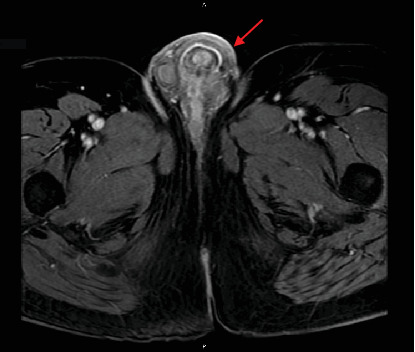

Background: Secondary penile cancer, despite the region's rich vascularization, is a rare phenomenon with only around 500 cases ever reported, typically of genitourinary origin and in even rarer cases, of colorectal adenocarcinoma. Unfortunately, the underlying mechanisms are not well elucidated, and prognosis remains poor with a late onset and median overall survival of 9 months for colon adenocarcinoma. Secondary penile cancer often presents alongside concurrent metastases months or years following successful treatment of the primary tumor. However, we report a case of an isolated penile metastasis as the presenting symptom of colon adenocarcinoma with no identifiable primary lesion or history of malignancy. Case Summary: A 67-year-old African-American male presented with a 1-month history of voiding symptoms, whereupon follow-up revealed a penile mass near the left base of the penis. Postoperative histopathological, immunohistochemical, and genomic analyses revealed characteristics of invasive and metastatic colorectal adenocarcinoma. Initial diagnostic testing revealed elevations in serum tumor markers CA 19-9 and carcinoembryonic antigen, while whole body PET/CT scan and colonoscopy failed to identify any tumorigenic lesions or primary colorectal malignancy. Although hypermetabolic activity was noted near the base of the penis and bilateral inguinal lymph nodes, the patient is currently on chemotherapy with a modified FOLFOX-6 regimen with active surveillance and no adverse effects. Conclusion: Here, we report a rare case of isolated penile metastasis as the first presentation of colon adenocarcinoma with no primary lesion. Regardless of origin, secondary penile cancer is a rare phenomenon with a poor prognosis. While the exact mechanism of spread is uncertain, the most probable mode of dissemination is through venous networks. There is also no standard of treatment relying on surgical, therapeutic, and palliative management. Although unclear, our unique presentation may portend a more favorable prognosis with continued treatment and observation.